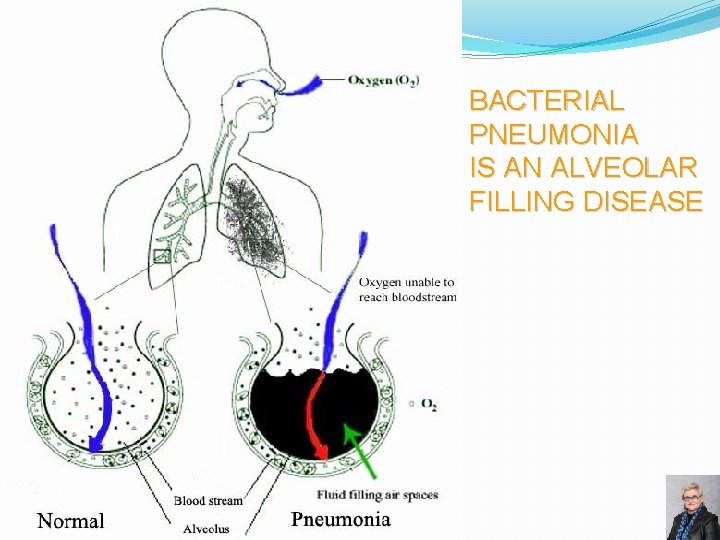

BACTERIAL PNEUMONIA IS AN ALVEOLAR FILLING DISEASE 55

LOBAR PNEUMONIA �Consolidation of entire lobe �Organisms: � Streptococcus pneumoniae (95%) � Klebsiella pneumoniae 56